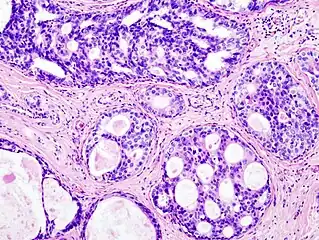

Histopathologic image from ductal cell carcinoma in situ (DCIS) of breast. Hematoxylin and eosin stain.